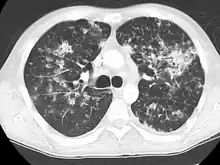

CT showing diffuse ground-glass opacities in periphery of both lungs in patient with COVID-19.

COVID-19

Ground-glass opacity is among the most common imaging findings in patients with confirmed COVID-19.[16][17] One systematic review found that among patients with COVID-19 and abnormal lung findings on CT, greater than 80% had GGOs, with greater than 50% having mixed GGOs and consolidation.[16] GGOs with mixed consolidation has most often been found in elderly populations.[18] Several studies have described a pattern among initial, intermediate, and hospital discharge imaging findings in the disease course of COVID-19. Most commonly, initial CT imaging reveals bilateral GGOs at the periphery of the lungs. During initial stages, this is most often found in the lower lobes, although involvement of the upper lobes and right middle lobe has also been reported early in the disease course.[16][18] This is in contrast to the two similar coronaviruses, SARS and MERS, which more commonly involve only one lung on initial imaging.[19][20] As the COVID-19 infection progresses, GGOs typically become more diffuse and often progress to consolidation.[11][18] This is sometimes accompanied by the development of a crazy paving pattern and interlobular septal thickening.[18] In many cases the most severe pulmonary CT abnormalities occurred within 2 weeks after symptoms began.[17] At this point, many individuals begin showing resolution of consolidation and GGOs as symptoms improve. However, some patients have worsening symptoms and imaging findings, with further increase in septal thickening, GGOs, and consolidation. These patients may develop lung "white-out" with progression to acute respiratory distress syndrome (ARDS) requiring treatment escalation.[17][21]

Preliminary reports have shown many patients have residual GGOs at time of discharge from the hospital. Due to the novelty of COVID-19, large studies investigating the long-term pulmonary CT changes have yet to be completed. However, long-term pulmonary changes have been seen in patients after recovery from SARS and MERS, suggesting the possibility of similar long-term complications in patients who have recovered from acute COVID-19 infection.[22]